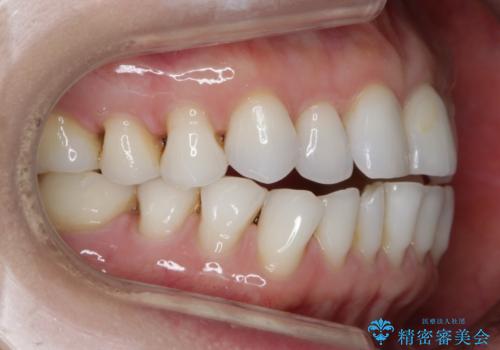

【非抜歯】マウスピースでオープンバイトを治す

- 歯ぎしりや食いしばり、噛み合わせの治療とガタつきを治したいとのことでご来院されました。

検査の結果、前歯と臼歯の高さに差があり、前歯が全く当たらない状態になっているため歯ぎしりによって奥歯が削れてしまっているという状態でした。

マウスピースの矯正装置を用い、ガタつきを治しつつ奥歯を沈めていくことで噛み合わせ全体の改善を図りました。